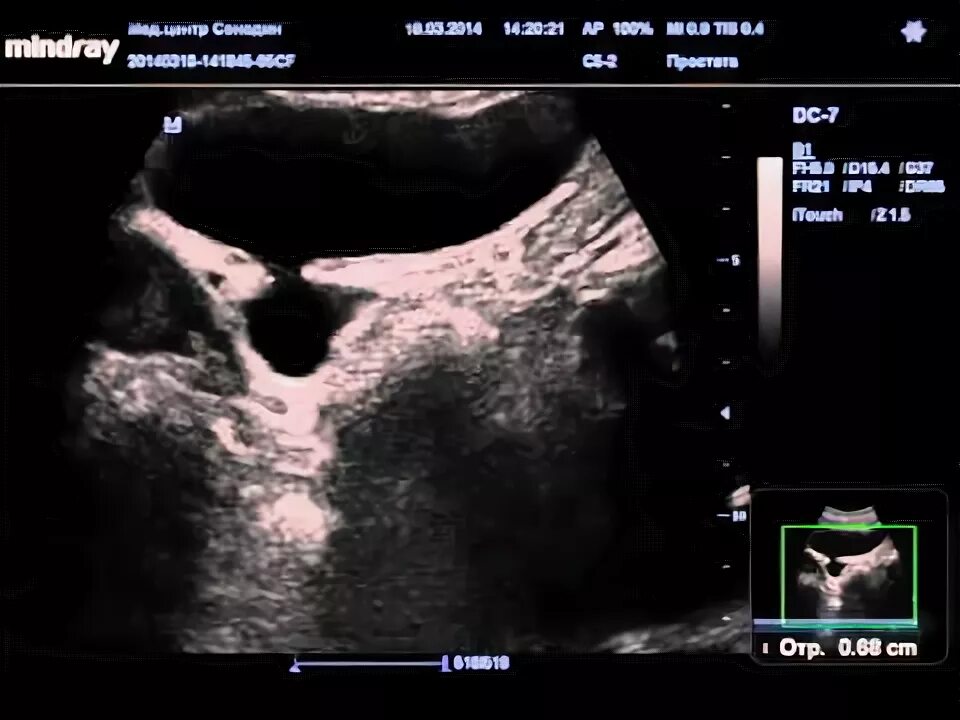

Дивертикул мочевого пузыря что это такое